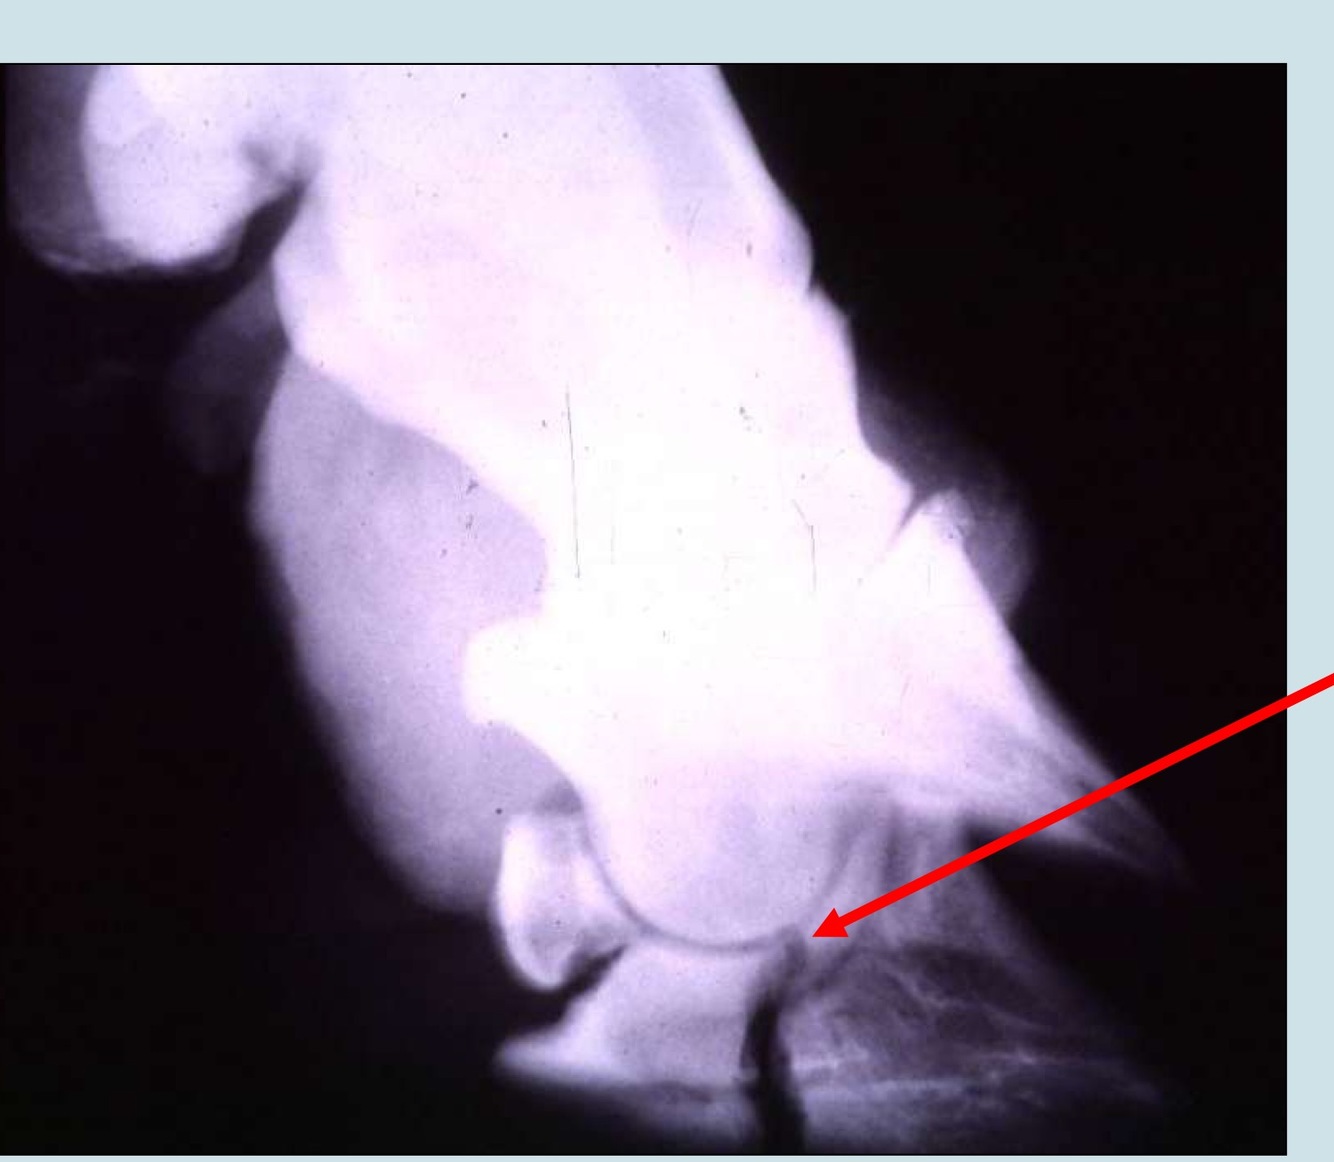

Diagnosis?

and preferred technique for treatment?

Articular fracture of P3;

closed technique for digit amputation

{as long as it’s noninfectious}